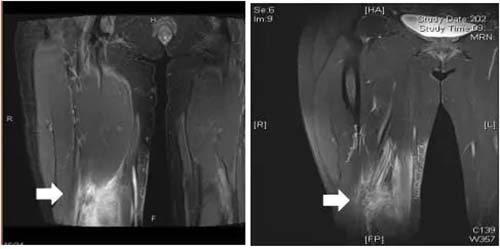

由此确定李女士是一例星型诺卡菌感染,LRBA基因突变可能是其发病基础。皮肤科持续使用复方磺胺甲恶唑及丙种球蛋白治疗。治疗第9天,李女士体温降至正常再无发热,红斑也逐渐消退(图6-8)。出院后,科室随访半年无复发。

图7 治疗1月后肌间水肿信号显著降低